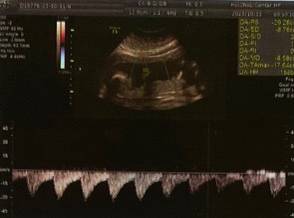

出院后,开启了两周一产检的日子

看着臭蛙崽子,一天天长大

终于,昨天崽子做了四维了,放心了一半~